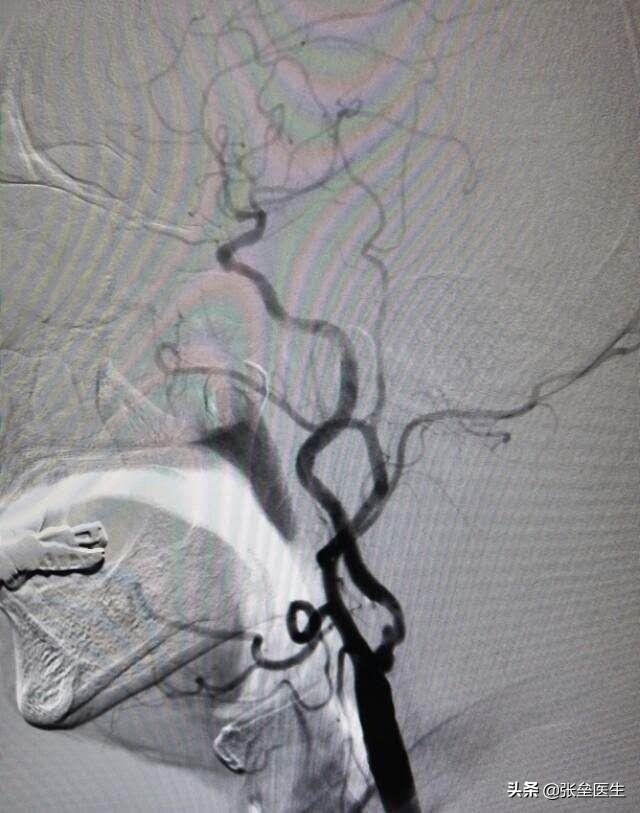

②脳血管撮影法もあるが、これは侵襲的な血管検査であり、一般的には好まれない。これは脳動脈の枝や開口部に動脈からアプローチするもので、カテーテルを脳動脈に送り込む。これは、造影剤を血管に注入してX線で見えるようにする方法で、血管に狭窄やプラーク、奇形があるかどうかをはっきりさせることができる。